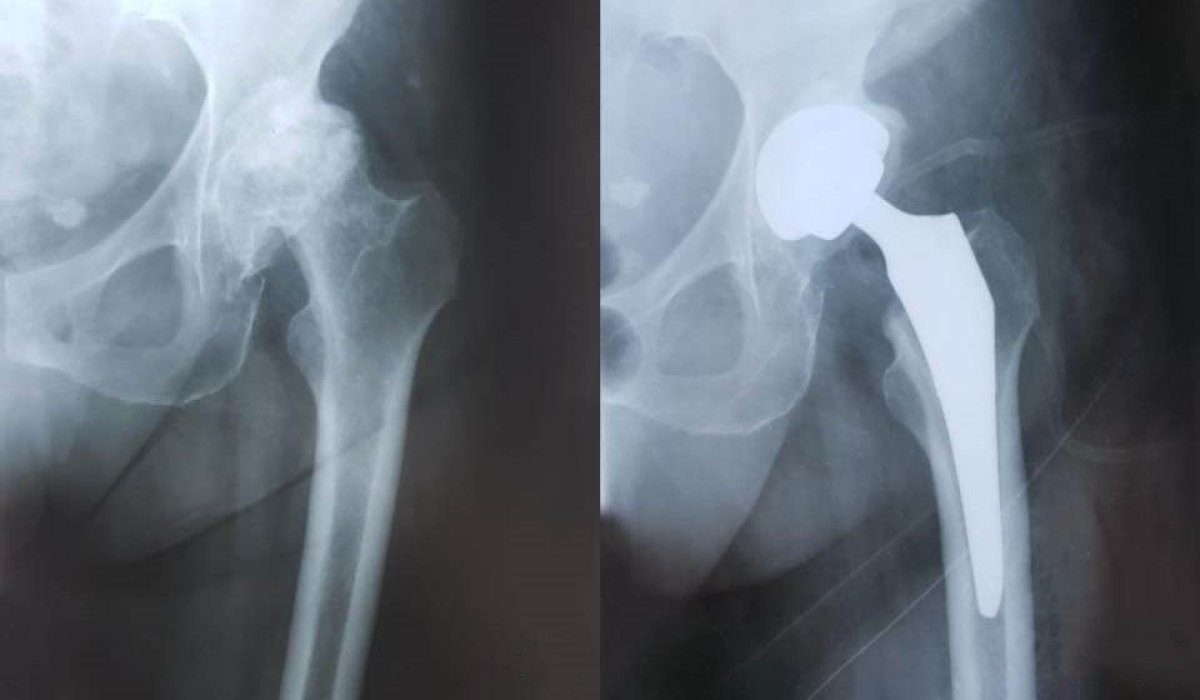

Життя після заміни кульшового суглоба: відновлення та поради лікарів

Життя після операції по заміні суглоба кульшового: нова реальність